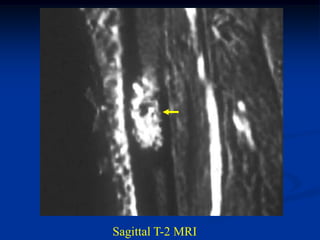

Sagittal T-1 MRI

Sagittal T-2 MRI